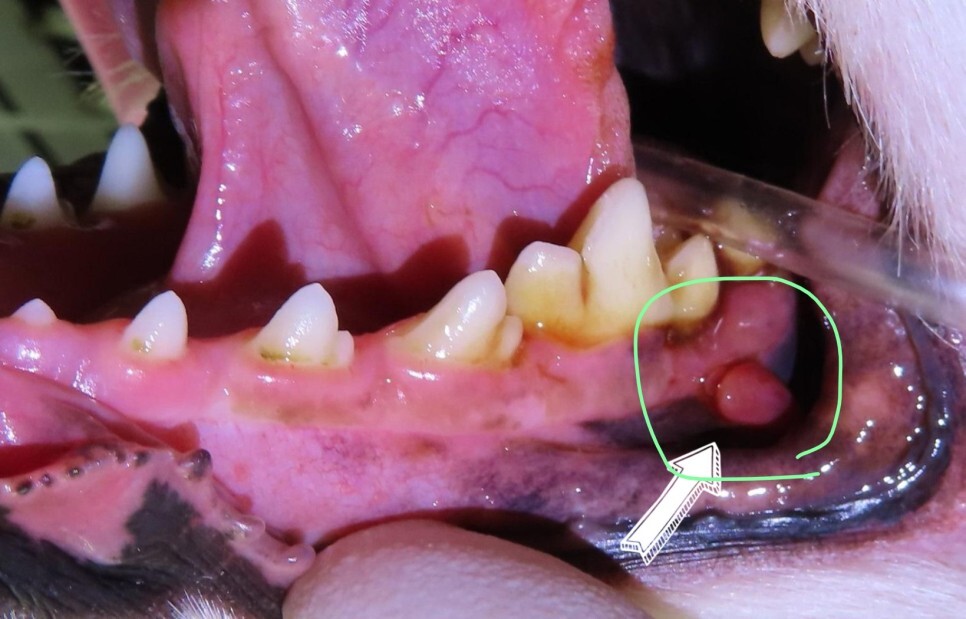

사진을 보면 치아 아래쪽 잇몸에 혹 비슷한 것이

관찰되고 있습니다.